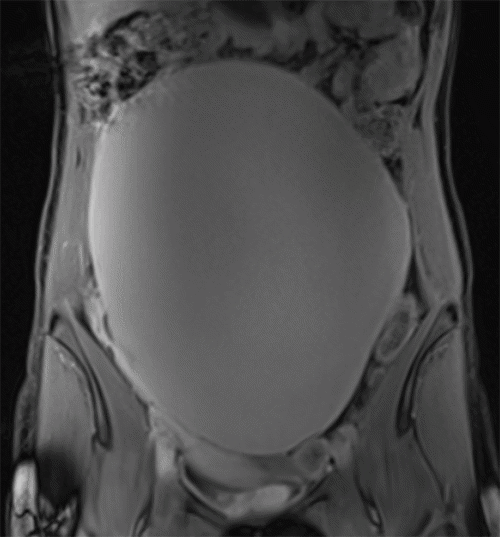

Several months prior to presentation, she experienced early satiety, abdominal bloating, and constipation, prompting medical evaluation. An abdominal ultrasound revealed a concerning 22 × 22 × 16 cm cystic structure abutting the uterine fundus. A follow-up pelvic MRI confirmed a large midline abdominal cystic lesion (Figure 1) but noted normal ovaries and a uterus separate from the mass. The lesion abutted the right ovary and uterus but did not appear to arise from them. Hyperintense foci, concerning for possible peritoneal seeding, were also identified (Figure 2).

Figure 1. MRI Pelvis with Large Intraabdominal Mass. Published with Permission